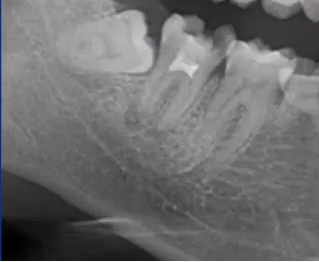

32岁,男性,因咬物不适来院就诊。

查:14残根,牙龈红肿;35叩诊(+),45叩诊(+),牙颌面见畸形中央尖。

35叩诊(+)

二次拍根尖片确认可看到根尖低密度炎症,临床检查与影像学检查相符,是根尖周炎。

曲面断层片怎么看口腔精读 | 一次性教你看懂曲面断层片!_https://www.jmylbn.com_新闻资讯_第21张